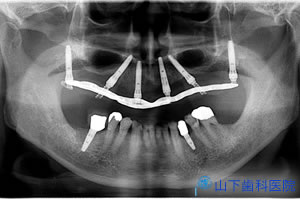

| 初診時のレントゲン写真です。 | ![]() |

| 5年経過後のレントゲン写真です。 | ![]() |